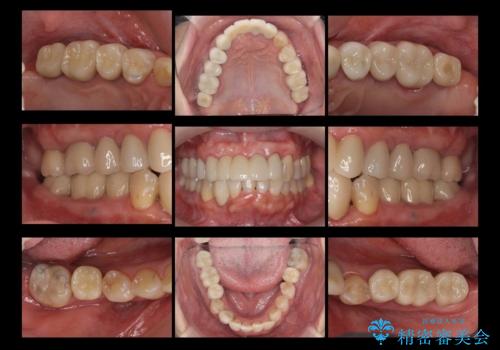

- 50代女性

- 2年

- 10-30回

- 全体的な虫歯治療、根管治療、および歯周病治療を行いました。

歯周病治療につきましては歯周ポケット除去のために歯周外科処置(APF)を行っています。

左下6の欠損については左下7はワイヤー部分矯正でアップライトを行い、補綴スペースを確保しています。

右下犬歯は歯周病の進行が重度のため、やむなく抜歯をし、骨増生後にインプラント埋入を行っています。

- 約660万円費用は治療当時の料金となります

根管治療は横浜桜木町歯科 大元先生が担当しました。

右下7の根管治療および再植は銀座院 林先生が担当しています。(抜歯は希望されなかったため、再植を行い、現在経過観察中です。)